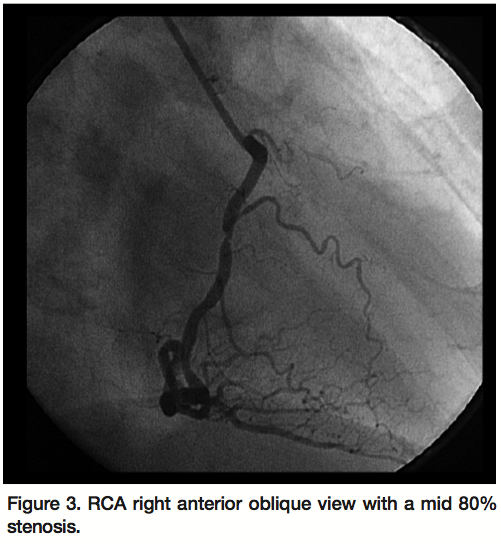

A 46-year-old white female with known coronary artery disease was admitted to a community hospital with a 6-week history of recurrent chest pain on exertion associated with left arm numbness and recurrent episodes of syncope and dyspnea on exertion. Laboratory workup revealed troponin of 0.4 ng/ml. She underwent a left heart catheterization, which revealed an 80% stenosis of the right coronary artery (RCA). Arterial puncture site was sealed using StarClose™ Vascular Closing System (Abbott Vascular). Subsequently, she was transferred to our facility for percutaneous intervention of the right coronary artery. On arrival, her vitals revealed a blood pressure of 154/85 mmHg and a heart rate of 82 bpm with regular rate and rhythm. She denied any chest pain or shortness of breath. The patient was taken for percutaneous coronary intervention of RCA.

exchange for a 6 Fr sheath. Close fluoroscopic inspection of the femoral artery area revealed part of a sheath (Figure 1). In order to retrieve the micropuncture sheath from the StarClose™ clip, the left femoral artery was cannulated and a snare was passed from this access site into the proximal right femoral artery. The micropuncture sheath was snared off the StarClose™ device and was safely retrieved through the left femoral artery (Figure 2). An aortogram and runoff images showed good distal leg blood flow without evidence of distal embolization or ischemia. Following this, RCA was successfully stented through the left femoral artery access site (Figures 3 and 4).